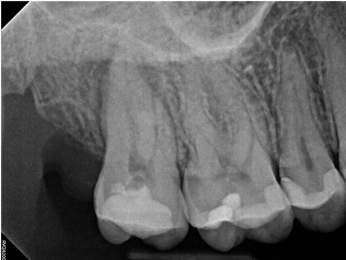

Fig 3. Case 1: CBCT showed a large lateral canal within the palatal root (Fig 3). There was a small preparation space, which was efficiently obturated (Fig 4). A small pinpoint of sealer in the middle of the palatal root indicated that the palatal lateral canal had been addressed (Fig 5). After 5 months, CBCT demonstrated complete healing (Fig 6), notably on the distal, where probing had resolved to 2 mm. Radiographic images were taken immediately postoperatively (Fig 7) and 5 months postoperatively (Fig 8).

Fig 4. Case 1: CBCT showed a large lateral canal within the palatal root (Fig 3). There was a small preparation space, which was efficiently obturated (Fig 4). A small pinpoint of sealer in the middle of the palatal root indicated that the palatal lateral canal had been addressed (Fig 5). After 5 months, CBCT demonstrated complete healing (Fig 6), notably on the distal, where probing had resolved to 2 mm. Radiographic images were taken immediately postoperatively (Fig 7) and 5 months postoperatively (Fig 8).

Fig 5. Case 1: CBCT showed a large lateral canal within the palatal root (Fig 3). There was a small preparation space, which was efficiently obturated (Fig 4). A small pinpoint of sealer in the middle of the palatal root indicated that the palatal lateral canal had been addressed (Fig 5). After 5 months, CBCT demonstrated complete healing (Fig 6), notably on the distal, where probing had resolved to 2 mm. Radiographic images were taken immediately postoperatively (Fig 7) and 5 months postoperatively (Fig 8).

Fig 6. Case 1: CBCT showed a large lateral canal within the palatal root (Fig 3). There was a small preparation space, which was efficiently obturated (Fig 4). A small pinpoint of sealer in the middle of the palatal root indicated that the palatal lateral canal had been addressed (Fig 5). After 5 months, CBCT demonstrated complete healing (Fig 6), notably on the distal, where probing had resolved to 2 mm. Radiographic images were taken immediately postoperatively (Fig 7) and 5 months postoperatively (Fig 8).

Fig 7. Case 1: CBCT showed a large lateral canal within the palatal root (Fig 3). There was a small preparation space, which was efficiently obturated (Fig 4). A small pinpoint of sealer in the middle of the palatal root indicated that the palatal lateral canal had been addressed (Fig 5). After 5 months, CBCT demonstrated complete healing (Fig 6), notably on the distal, where probing had resolved to 2 mm. Radiographic images were taken immediately postoperatively (Fig 7) and 5 months postoperatively (Fig 8).

Fig 8. Case 1: CBCT showed a large lateral canal within the palatal root (Fig 3). There was a small preparation space, which was efficiently obturated (Fig 4). A small pinpoint of sealer in the middle of the palatal root indicated that the palatal lateral canal had been addressed (Fig 5). After 5 months, CBCT demonstrated complete healing (Fig 6), notably on the distal, where probing had resolved to 2 mm. Radiographic images were taken immediately postoperatively (Fig 7) and 5 months postoperatively (Fig 8).

In the first case study, a young female patient was told she had a tooth (tooth No. 2, Figure 3) that should be extracted due to extensive bone loss. Using CBCT, the clinician was able to identify a large lateral canal within the palatal root. Despite the bone loss, the patient was eager to save her tooth. He offered to treat the tooth with the broad-spectrum acoustic technology. As shown in Figure 4, the preparation space was much smaller, which he was able to obturate efficiently. In addition, the small pinpoint of sealer in the middle of the palatal root indicated that the palatal lateral canal had been addressed (Figure 5). In the clinician's opinion, this area was likely the primary source of much of the bone loss.

Figure 6 through Figure 8 demonstrate that, 5 months after the procedure, complete healing had occurred, notably on the distal, where the probing had resolved to 2 mm. The patient then had a crown placed by her general dentist. Given her positive experience with the technology, she was eager to return as needed for continued follow-up.